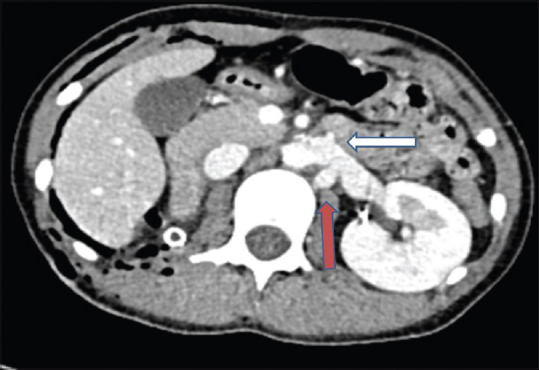

We present a case of inadvertent left renal vein clipping during right retroperitoneoscopic nephrectomy (RPN) and describe its expeditious identification and management. A 13-year-old girl underwent RPN for nonfunctioning kidney due to urolithiasis. During the dissection of the right renal vein, the inferior vena cava (IVC) got lifted off the parietal wall and the left renal vein was mistakenly ligated. Based on a strong intra-operative suspicion, the patient underwent an urgent computed tomography angiography which confirmed the ligation of the left renal vein. The patient was reoperated immediately and an end-to-side anastomosis was performed between the left renal vein and the IVC.